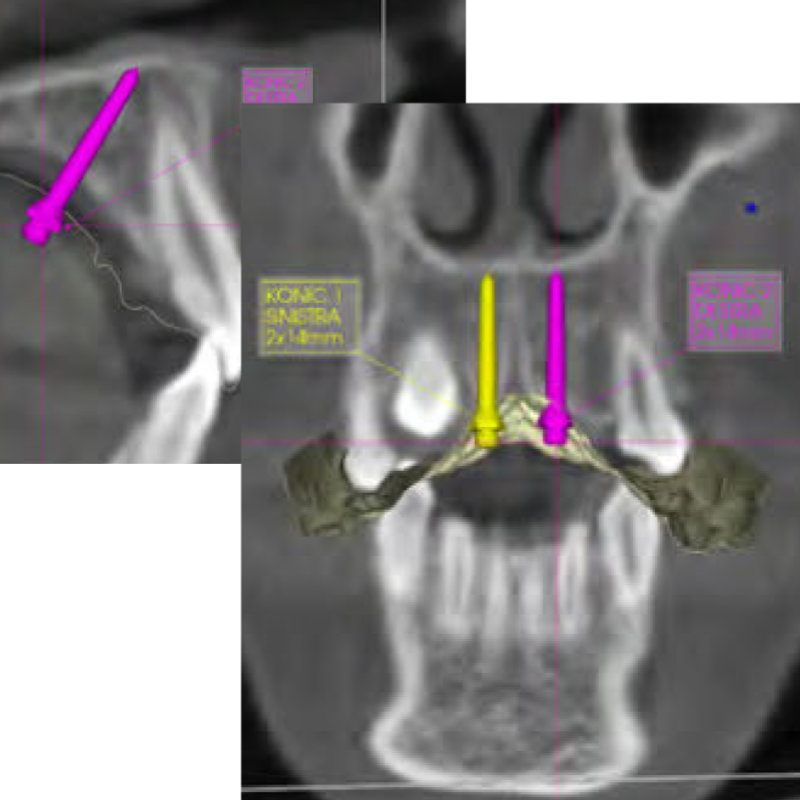

Die Spider Screw RP Konic ist speziell für die kieferorthopädische skelettale Verankerung im Gaumendach ausgelegt.

Die zylindrisch-konische Form und ideale Höhe des kieferorthopädischen Kopfs gewährleisten eine geeignete Auflagefläche für laterale Belastungen und erleichtern das Einsetzen von angepassten Produkten insbesondere im Falle von Disparallelität.

Der transmukosale Teil ist glatt und konisch, um optimale Schleimhauthaftung zu gewährleisten und Gewebeirritation zu vermeiden.

Am Kopf der Spider Screw können zusätzliche Produkte befestigt werden. Sie ist in zahlreichen Größen erhältlich, um jeder Planung gerecht zu werden.

Als einen ganz besonderen Service bietet HDC Unterstützung in Form von geplante Bohrschablonen, Modellen und individuell hergestellter Apparaturen (Laser-Sinter-Verfahren) über das DPRI CAD/CAM Portal.

Über dieses Portal kann zudem direkt mit den Experten ein Austausch stattfinden

(z.B. Planungsfragen klären) und später auf die entsprechenden Daten jederzeit zugegriffen werden.